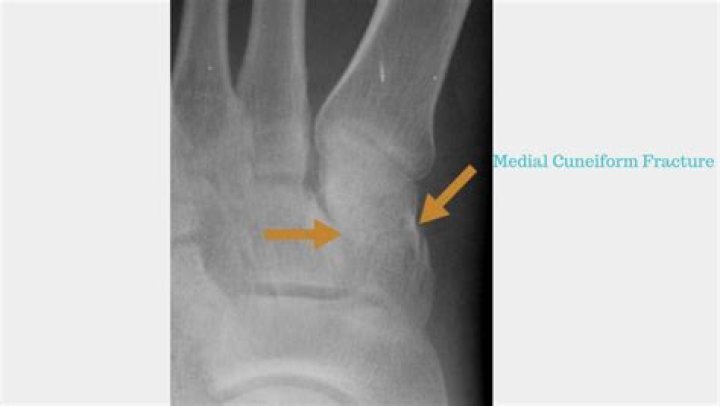

Isolated fractures of the cuneiform bones are rare, and even since the development of advanced diagnostic imaging techniques, reports of isolated fractures remain scarce.

Isolated fractures of the cuneiforms are extremely rare, accounting for only 1.7% of all midfoot fractures.